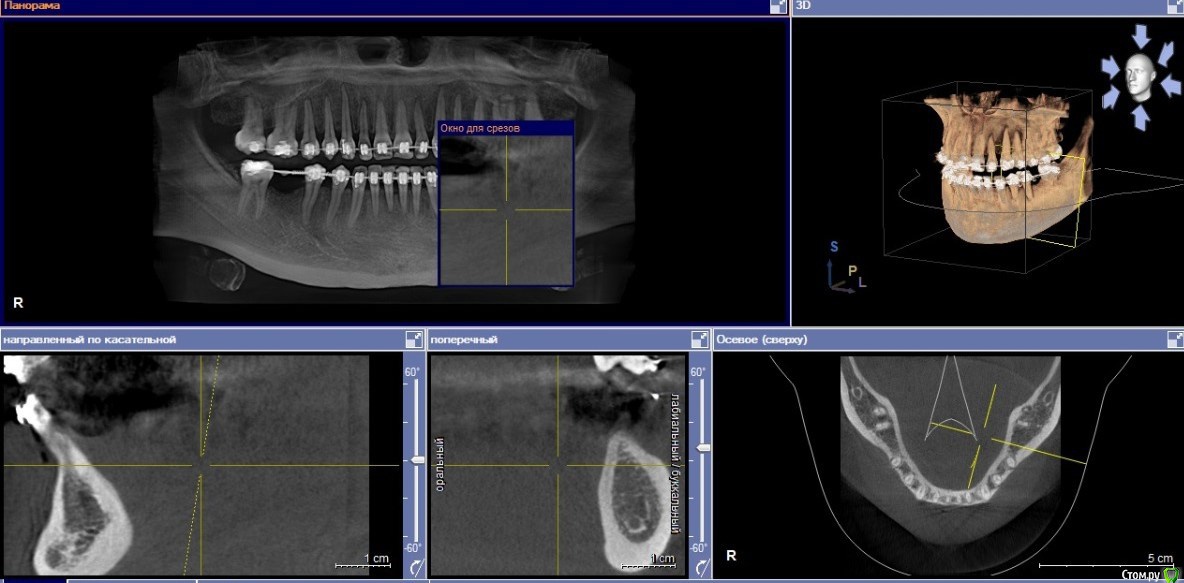

my_evid Опубликовано 15 ноября, 2019 Поделиться Опубликовано 15 ноября, 2019 Здравствуйте! Прошу высказать свое профессиональное мнение на мою ситуацию. Заканчиваю ортодонтическое лечение, 15 лет отсутствуют 46 и 36, мне сообщили о необходимости установки имплантов для дальнейшего сохранения результата. В итоге у трех хирургов разное мнение на этот счет: 1. необходима костная пластика по бокам и под имплантатом (с установкой костного блока) (вроде)2. костная пластика необходима по бокам3. костная пластика не нужна. Как мне объяснил врач, придерживающийся третьего варианта, костная пластика необходима в моем случае для того чтобы коронка была одинакового размера с остальными зубами, это важно только для эстетики, на жевательную способность это не влияет, а так, есть возможность имплантат вогнать глубже и обойтись без этой операции.Врач, придерживающийся второго варианта, сказал что тоже сделаем глубже имплантат, коронки будут отличаться по высоте, но пластика нужна по бокам, как я поняла, непосредственно для его установки.Так как это дополнительные средства и дополнительное вмешательство, не знаю как поступить. Сделала скрин КТ, надеюсь что-то будет ясно. Ссылка на комментарий

Irouil Опубликовано 15 ноября, 2019 Поделиться Опубликовано 15 ноября, 2019 Надо замеры делать на кт, но, на первый взгляд, возможны два последних, из перечисленных Вами, варианта, первый кажется чрезмерным Ссылка на комментарий

krokomot Опубликовано 15 ноября, 2019 Поделиться Опубликовано 15 ноября, 2019 На мой взгляд костная пластика вам не нужна, возможно потребуются действия с мягкими тканями, для улучшения окружающих коронку структур. Ссылка на комментарий